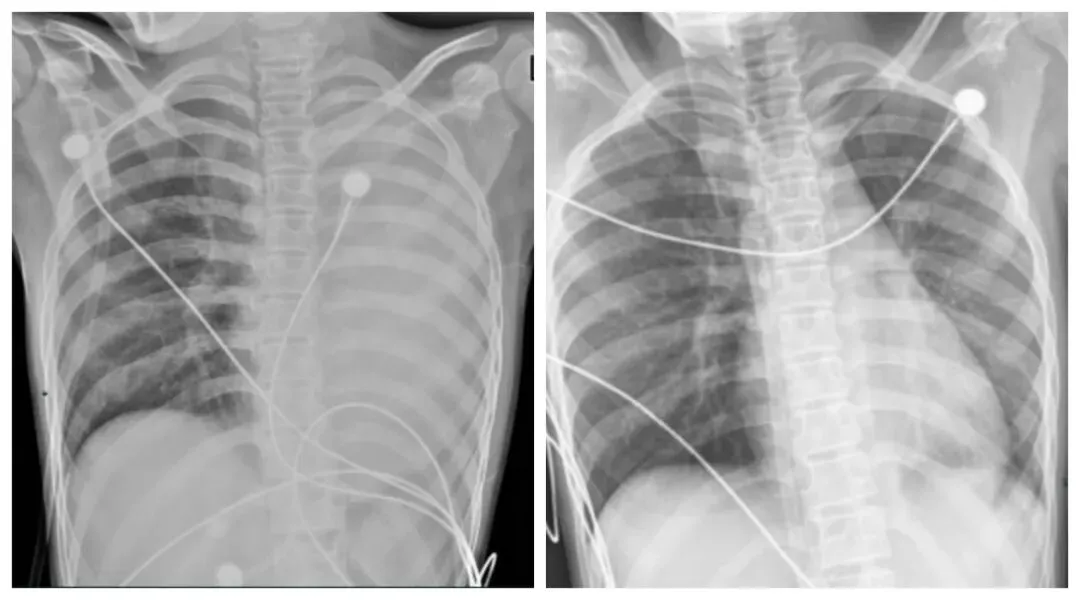

一开始,她只是轻微咳嗽,发热后在外院检查提示肺炎、肺不张,转诊到浙大四院儿科时,笑笑出现呼吸急促、胸闷胸痛,血氧饱和度勉强维持在 90% 左右,胸片显示左肺已完全呈 “白肺” 改变,病情急剧恶化。

胸片或CT提示“肺不张” “肺实变”;